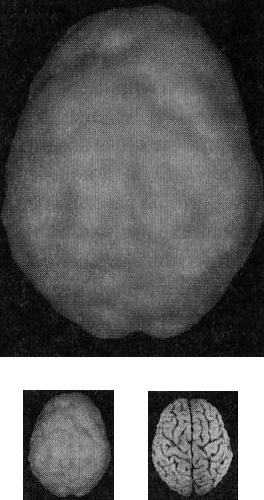

В этой книге используют трехмерные снимки мозга двух видов. Первый — это трехмерные снимки поверхности, которые фиксируют верхние 45 % активности мозга. На них показано кровообращение в коре мозга и подкорковых областях. По этим снимкам мы определяем области нормального кровообращения и области со сниженным доступом крови. С помощью таких томограмм выявляют инсульты, травмы и ущерб от наркотиков. Снимок здорового мозга должен показать ровную симметричную активность по всей поверхности коры мозга (рис. 2.1 и 2.2).

Трехмерное изображение поверхности здорового мозга ОЭКТ (вид поверхности сверху и снизу)

Рис. 2.1 Вид сверху

Полная симметричная активность

Рис. 2.2 Вид снизу

Сниженная активность выглядит на подобных сканах как дыра или вмятина. Эти «дыры» и «провалы» не означают, что активность мозга в этих местах совсем на нуле, она просто снижена, так как компьютер настроен показывать только верхние 45 % активности. Все, что меньше этого значения, выглядит как дыра или вмятина. Порог в 45 % выбран, поскольку он соответствует двум стандартным отклонениям от нормы[1] и, согласно нашим данным и данным других исследователей, является оптимальным для диагностических целей.

Второй тип томограмм — это трехмерные функциональные снимки, в которых компьютер сначала вычисляет среднюю активность мозга, а затем показывает верхние 15 % активности. Они помогают увидеть гиперактивные области, что полезно в диагностике припадков, разных типов тревожности и депрессии.

Здоровый трехмерный функциональный снимок (рис. 2.3 и 2.4) должен показывать активность (белым цветом) в задней части мозга (мозжечке) и визуальной, или затылочной, коре и среднюю активность в остальных местах (показано сеткой).

Трехмерное изображение функциональной активности здорового мозга ОЭКТ (вид поверхности сверху и снизу)

Рис. 2.3 Вид сверху

Мозг. От хорошего к превосходному

Рис. 2.4 Вид сверху

Примечание: В тексте книги будут использоваться иконки, которые помогут читателю понимать сканограммы и увидеть их отличия от нормы. Рис. А состоит из двух иконок: трехмерного изображения поверхности здорового мозга, вид сверху; и модели мозга с той же самой перспективы.

Рис. Б показывает трехмерный снимок поверхности здорового мозга, вид снизу, а нижняя иконка — это модель мозга с той же перспективы.

Рис. В показывает трехмерную картину активности здорового мозга, вид сверху, а ниже показан мозг в этой проекции.